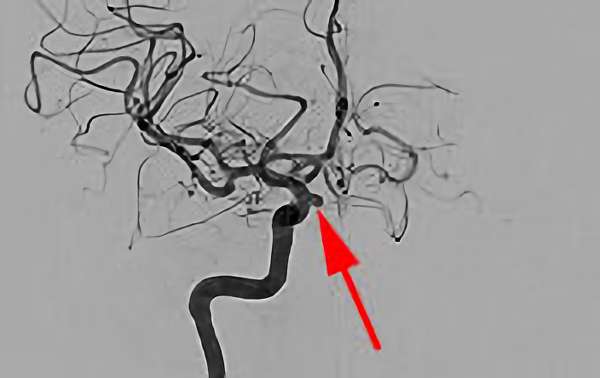

No.1631 手術前